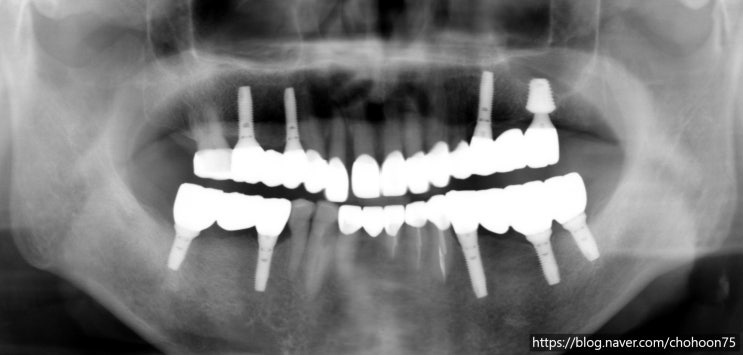

안녕하세요. 조훈 치과입니다. 오늘은 앞서 2021년 6월 조훈 치과 블로그에 포스팅하였던 케이스로 최근의 ...